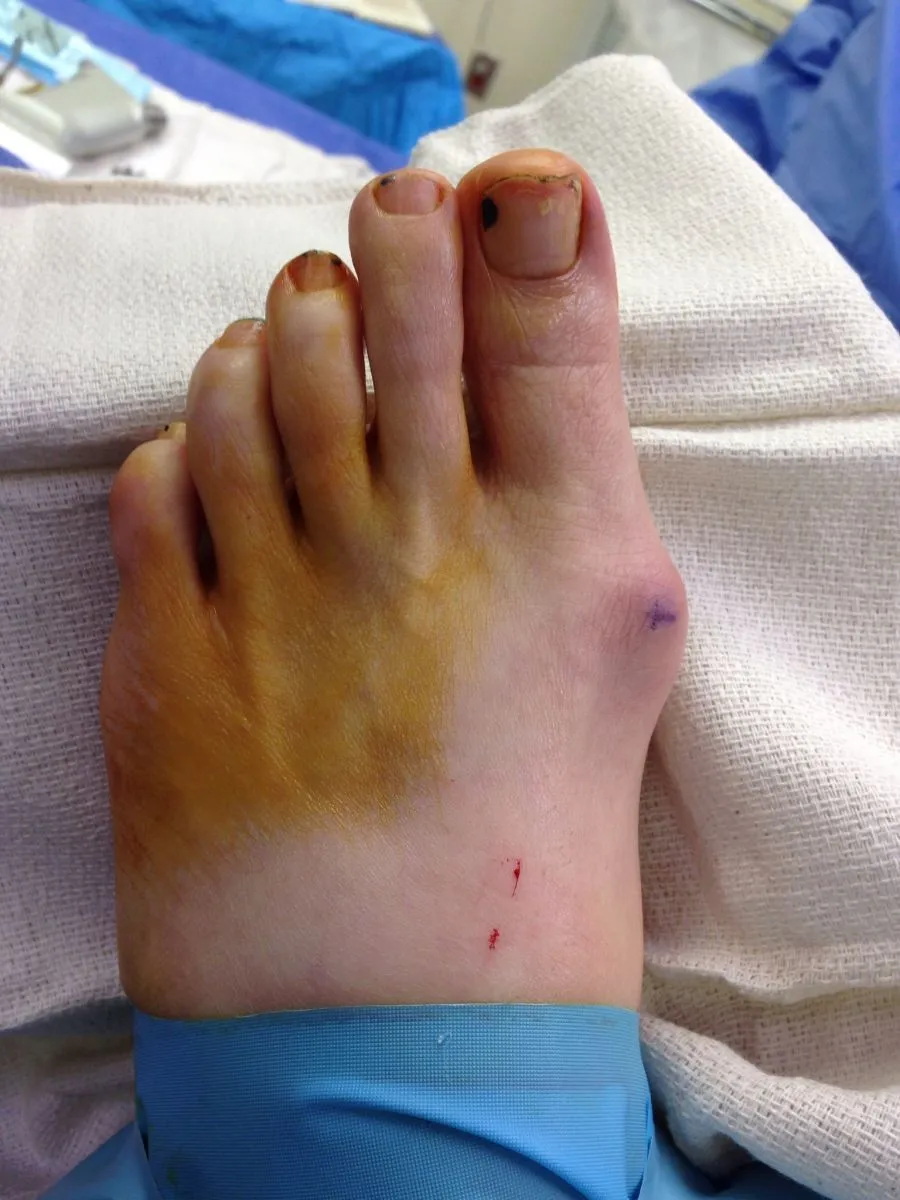

Preop Clinical Pics

Pre and Immediate Intraop Clinical Pictures and X-rays Status Post Medial Approach Bunion with first metatarsal head osteotomy

Pre and Immediate Postop Pic

Before and Immediate Intraop Postop Clinic pic

Pre and Immediate Post Op Pics of Bunionectomy with First Metatarsal Osteotomy